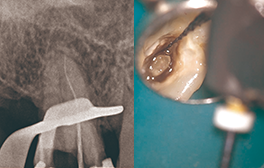

• Edge GlidePath™、EdgeTaper Platinum™、EdgeSequel Sapphire™を使用して二重湾曲根管の形状を残したまま、根管形成を行った例。

エッジグライドパスを使用

Edge GlidePath™

エッジテーパープラチナムを使用

EdgeTaper Platinum™ in MB

XPエンドシェイパーとエッジシークエルサファイアを使用

XP-Endo Shaper(白水貿易)+EdgeSequel Sapphire™ in MB1 & MB2

エッジシークエルサファイアを使用

#35/.04 EdgeSequel Sapphire™